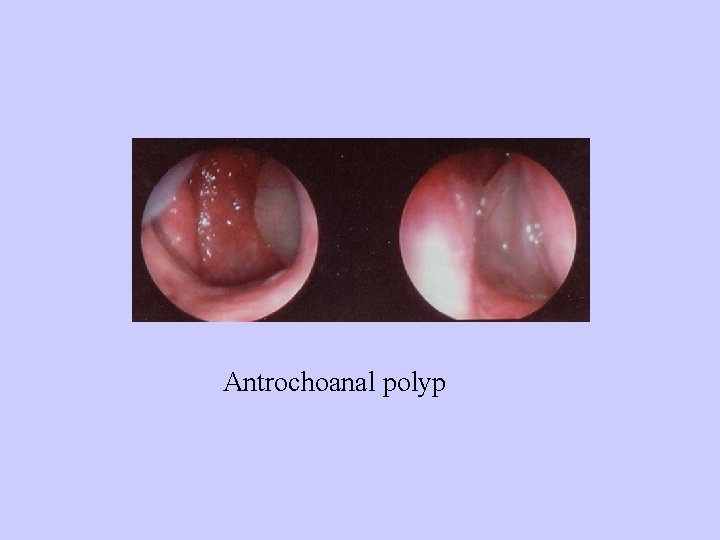

Antrochoanal polyp